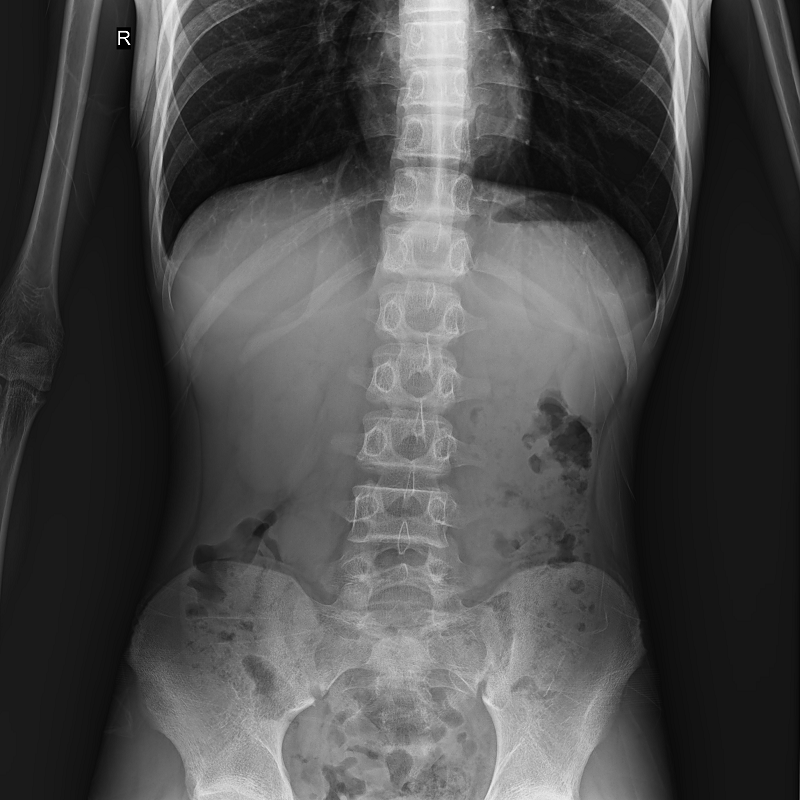

●呈現(xiàn)全下肢或全脊柱圖像

●在脊柱及下肢畸形矯正手術(shù)治療中,為術(shù)前方案制定和術(shù)后復(fù)查提供精準(zhǔn)測量

●有效解決傳統(tǒng)X光片不能一次成像問題,為患者提供更加優(yōu)質(zhì)的醫(yī)療服務(wù)

點(diǎn)片裝置可實(shí)現(xiàn)大范圍縱向移動,高效完成各部位、全身拼接等檢查需求